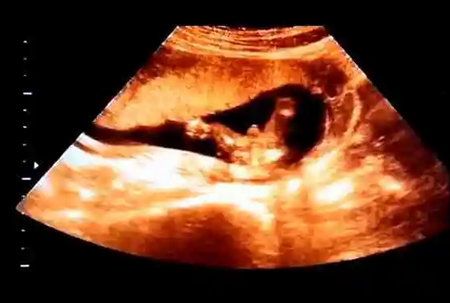

前期准备 (约 5000 元): 包括病史询问、体检、基础血常规检查等。 药物促排卵 (约 1.5 万元): 根据医生的指导,进行药物注射来促进卵巢发育和卵子成熟。 取卵手术 (约 3000 元): 在超声引导下通过阴道取卵,获取成熟的卵子。 精子处理 (约 2000 元): 选择优质精子进行筛选和处理,以提高受精成功率。 胚胎培养 (约 5000 元): 将卵子和精子结合培养,观察胚胎发育情况。 胚胎移植 (约 4000 元): 将优良胚胎移植到女性宫腔内。整个供精试管流程约需一个月至两个月的时间做到。在胚胎移植后的14天左右,可以进行检测来评判是否是成功怀胎。